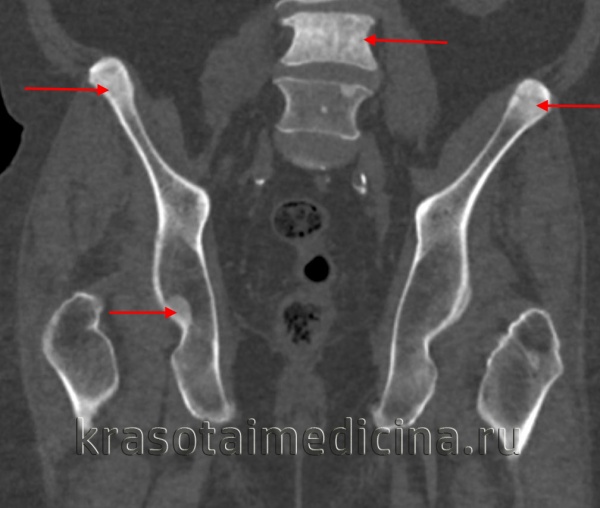

Для уточнения диагноза назначают рентгенологическое исследование плоских и трубчатых костей: рентгенографию черепа, рентгенографию позвоночника, рентгенографию бедер и т. д. На всех снимках выявляется резкое уплотнение костной ткани. Эпифизарные отделы трубчатых костей закруглены и утолщены, в области метафизов определяются булавовидные утолщения. Все кости непрозрачны для рентгеновского излучения, кортикальный слой и костномозговой канал не просматриваются. Иногда в метафизарных областях обнаруживаются участки поперечного просветления.

Для диагностики врожденного семейного остеопетроза применяют рентгенологические методики, общие анализы крови, молекулярно-генетические исследования, изучение наследственного анамнеза больного. На рентгенограммах выявляют общее уплотнение костной ткани (диффузный остеосклероз), выраженность которого больше при аутосомно-рецессивных вариантах заболевания. В некоторых элементах скелета (фаланги пальцев, подвздошные кости, позвонки) остеопетроз имеет очаговый характер, создавая характерную рентгенологическую картину, известную как «кость в кости». В длинных трубчатых костях изменяется форма метафизов и размеры костномозгового канала – от незначительного уменьшения при доброкачественном типе врожденного семейного остеопетроза до практически полного исчезновения при рецессивном. На рентгенограммах также могут выявляться признаки гидроцефалии, искривления позвоночника, у взрослых – следы многочисленных заживших переломов.

На рентгеновских снимках выявляется генерализованный остеосклероз. Кости имеют гомогенную структуру, костномозговой канал отсутствует. Метафизы длинных трубчатых костей булавовидно расширены. На рентгенограммах черепа определяется склероз и уменьшение пневматизации синусов. Поздний остеопетроз наследуется по аутосомно-рецессивному типу и проявляется теми же симптомами, однако, заболевание манифестирует в возрасте 10 лет или позже и отличается меньшей распространенностью остеосклероза.